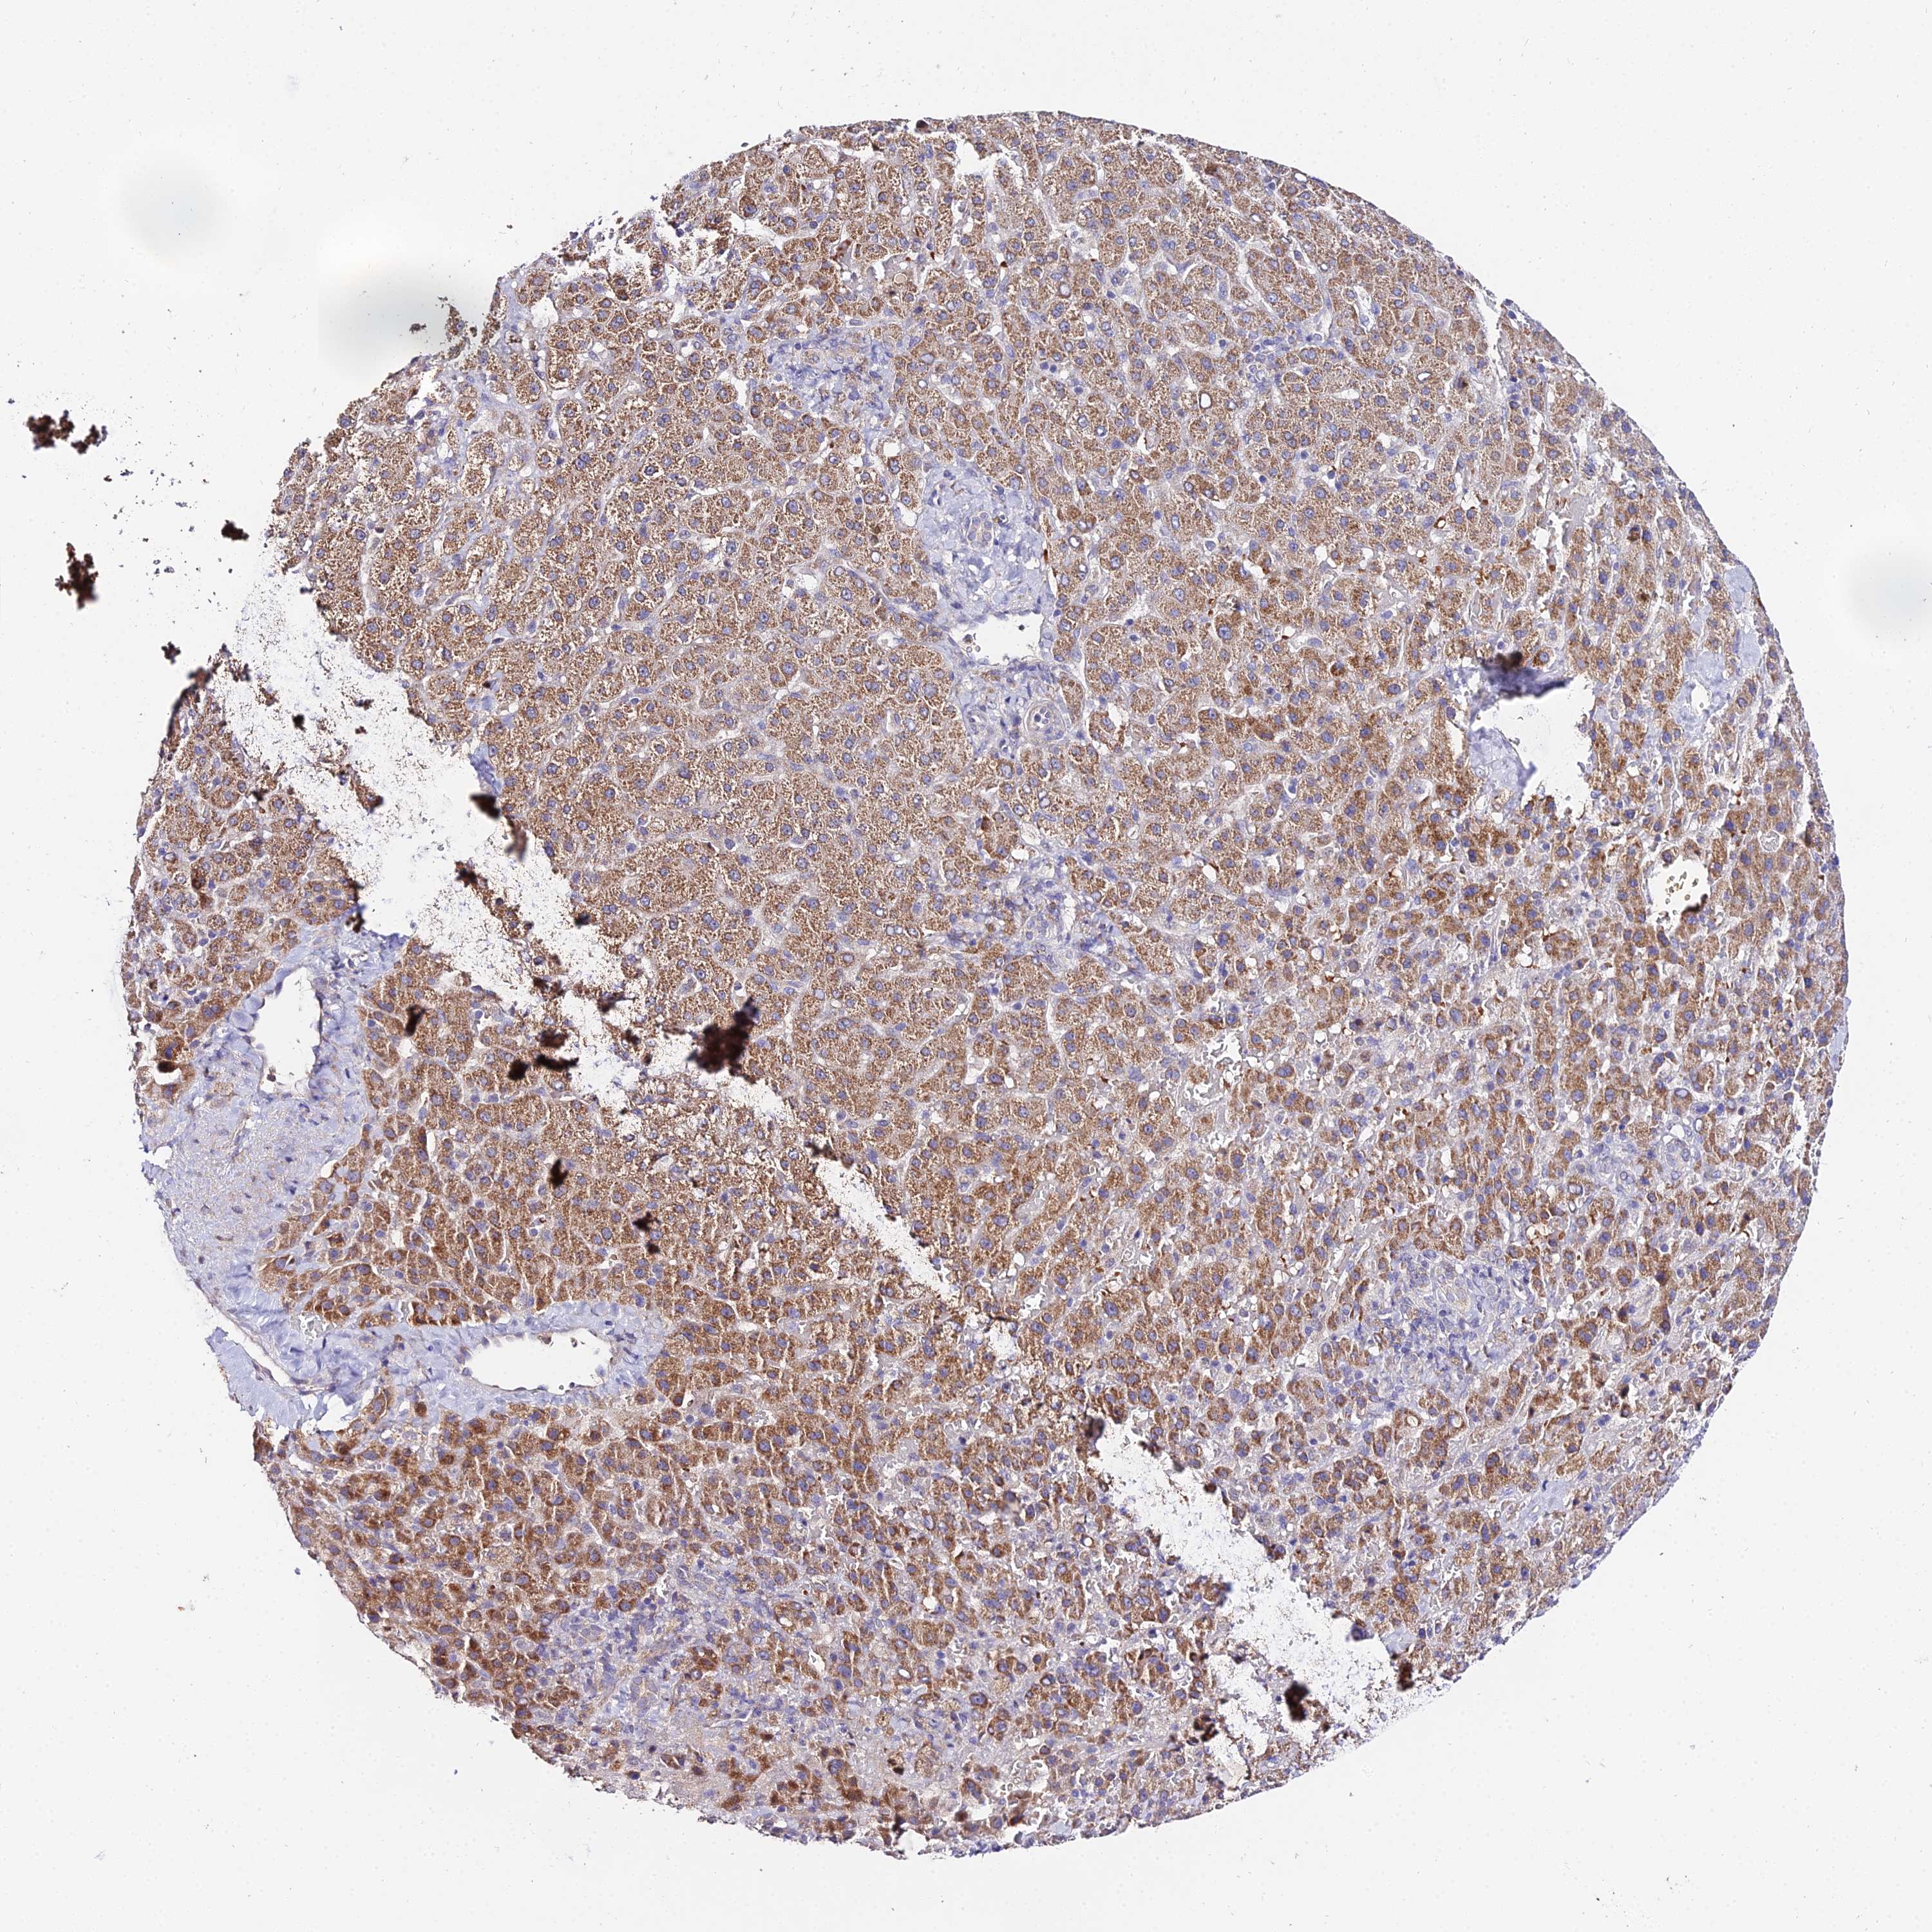

LIVER CANCER - Protein expressioni

A mouse-over function shows sample information and annotation data. Click on an image to view it in a full screen mode. Samples can be filtered based on level of antibody staining by selecting one or several of the following categories: high, medium, low and not detected. The assay and annotation is described here.

Note that samples used for immunohistochemistry by the Human Protein Atlas do not correspond to samples in the TCGA dataset.

Antibody stainingi

Antibody staining in the annotated cell types in the current human tissue is reported as not detected, low, medium, or high, based on conventional immunohistochemistry profiling in selected tissues. This score is based on the combination of the staining intensity and fraction of stained cells.

Each image is clickable and will lead to virtual microscopy that enables deeper exploration of all samples and also displays staining intensity scores, fraction scores and subcellular localization as well as patient and tissue information for each sample.

Antibody HPA042994

Staining

High

Medium

Low

Not detected

Intensity

Strong

Moderate

Weak

Negative

Quantity

>75%

75%-25%

<25%

None

Location

Nuclear

Cytoplasmic/membranous

Cytoplasmic/membranous,nuclear

Cholangiocarcinoma

Carcinoma, Hepatocellular, NOS